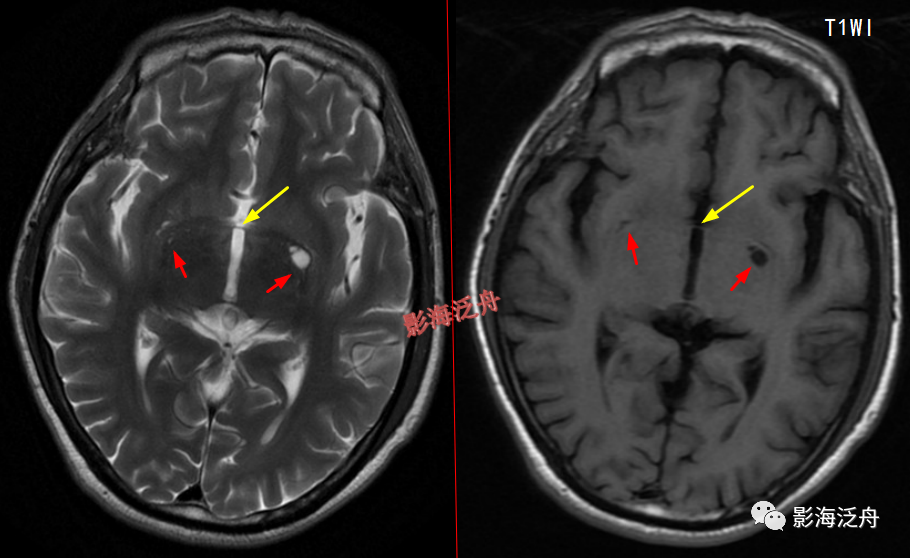

当脱髓鞘改变呈片状且沿着侧脑室周围对称性分布时,大家往往一眼就能识别出来,像上图这种双侧半卵圆中心多发非特异性脱髓鞘病灶,大家可能就有点心虚了。注意最大的一个病灶(黄箭)长轴平行于侧脑室(红线),所以只是普通的退变,而不是不是MS。

当这种非特异性脱髓鞘病灶比较局限、散发的时候,如何与VR腔隙及腔梗灶区分呢?一般来说,前者显示比后两者更加浅淡和模糊,在T1WI序列尤为明显。